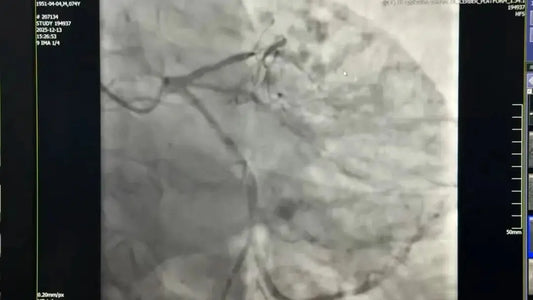

On October 17, a team led by Dr. Yang Haitao in Beijing showcased groundbreaking advancements in the treatment of atrial fibrillation (AF) with an innovative combination of ultra-high-density mapping and...